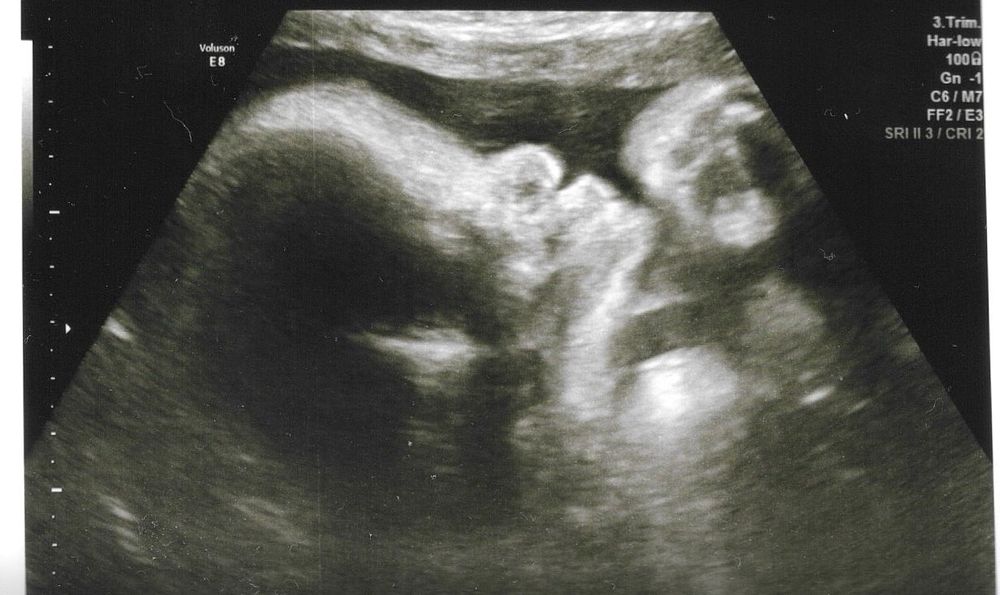

33,2 УЗИ 3D

Мой ВикторУЗИ 33,2 (по фетометрии 33,0)

По итогу в записях ОГ доношенного ребенка (35,7 см), прирост от предыдущего экспертного УЗИ за 9 дней 4,5 см. Выглядит абсурдно. Буду звонить в центр, просить посмотреть на аппарате значения. Если откажут, то ничего делать не буду, так как уже успокоилась. Дождусь следующего УЗИ в 35 недель.

UPD: конечно врач сделала ошибку в заключении, обхват головы 327мм